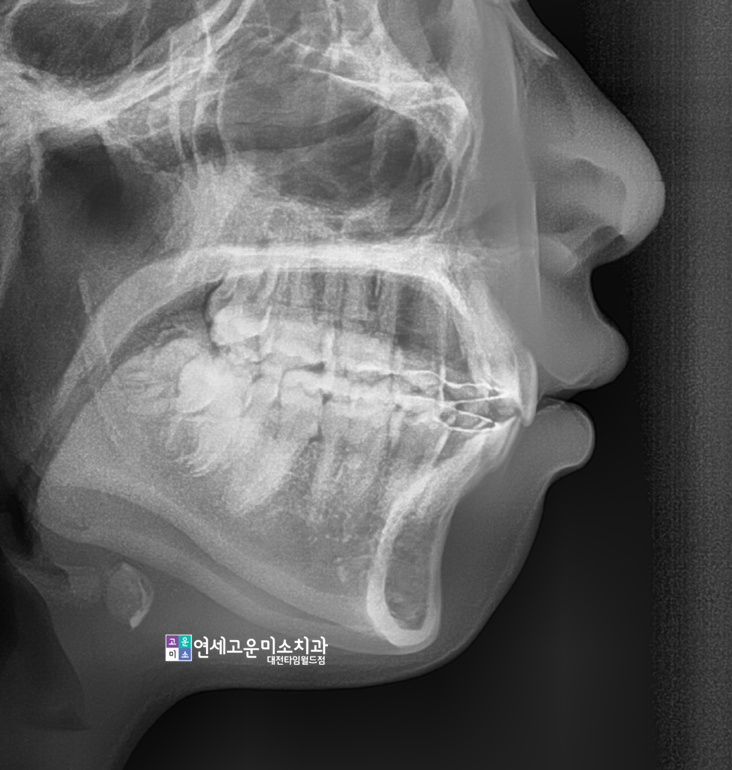

발치 case) 입이 돌출돼서 해결하고 싶어요

코에서 입술로 이해되는 각도가

심한 예각을 이루고 있고

무턱이 심한 것을 알 수가 있습니다.

돌출입 환자분들의 전형적인 특징이

입술을 자연스럽게 다물기 힘들기 때문에

"호두턱양상"이 나타납니다

이렇게 돌출입이면서 무턱이신 분들은

보통 발치치료를 진행하게 됩니다.